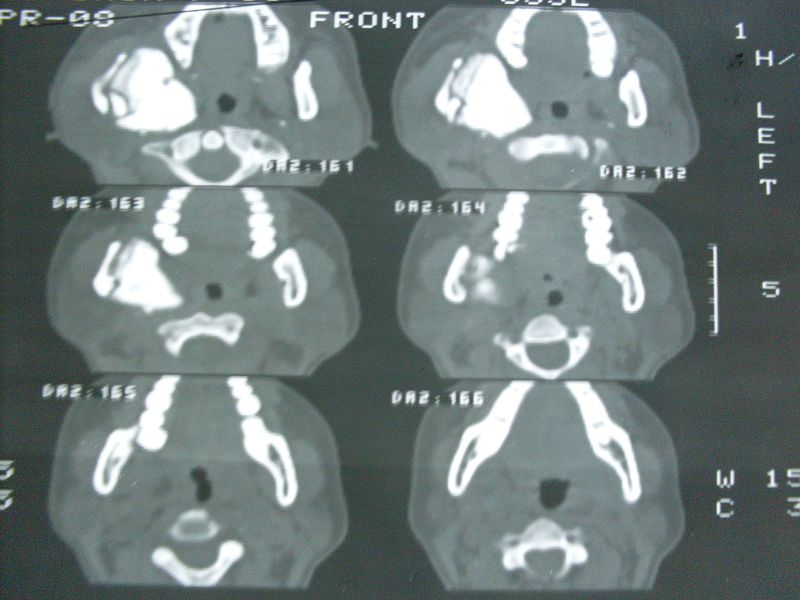

标题: CT12916:求助 F/44 右聂部肿痛一年余 [打印本页]

标题: CT12916:求助 F/44 右聂部肿痛一年余

是什么肿瘤

单骨病变,考虑非骨化纤维瘤可能

支持右侧下颌骨升支骨化性纤维瘤.

右侧下颌骨升支单骨病变,考虑非骨化纤维瘤可能。图片模糊,期等结果。

单骨病变,考虑骨化纤维瘤可能,与骨纤鉴别就此点

骨纤可能性大,不能除外骨化性纤维瘤。